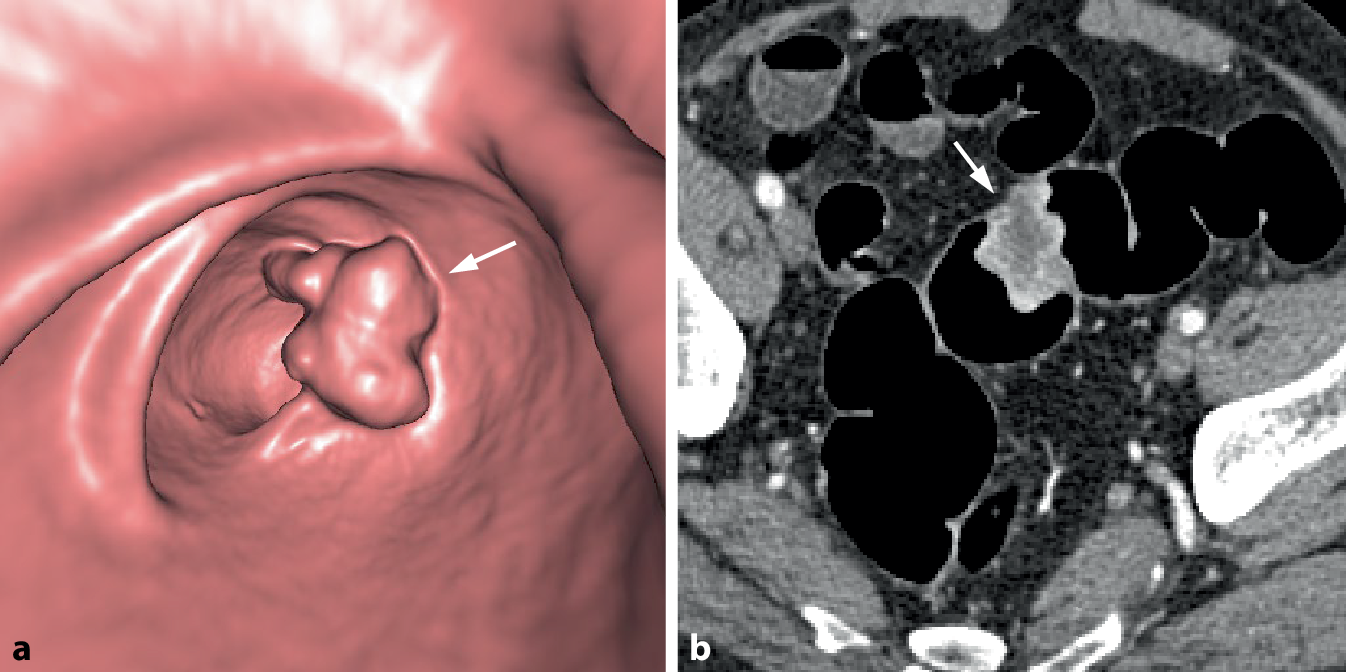

Das zentrale radiologische Befundkriterium kolorektaler Karzinome ist die fokale tumoröse Wandverbreiterung des Dickdarms. Diese manifestiert sich typischerweise in Form einer zirkulären oder semizirkulären, oftmals stenosierenden Wandverbreiterung oder aber als fokale polypoide Raumforderung (Abb. 1).

Abb. 1

Wesentliche Befundkriterien der CT-Kolonographie (CTK) des kolorektalen Karzinoms (KRK)

Bei polypösen Tumoren finden sich meist große, breitbasige, sessile Raumforderungen von über 3 cm Größe, typischerweise mit einem lobulierten Aspekt (Abb. 5). Durch Tumornekrosen kann es zur Ausbildung von Ulzerationen kommen.

Abb. 5

Polypoides Karzinom im Colon sigmoideum. a Die endoluminale 3D-Ansicht einer polypoiden Raumforderung mit lobuliertem Aspekt (Pfeil). b Das axiale 2D-Bild zeigt eine fokale polypoide Wandverbreiterung mit weichteildichter Struktur nach Kontrastmittelapplikation (Pfeil). Die zentrale Hypodensität spricht für eine muzinöse Komponente